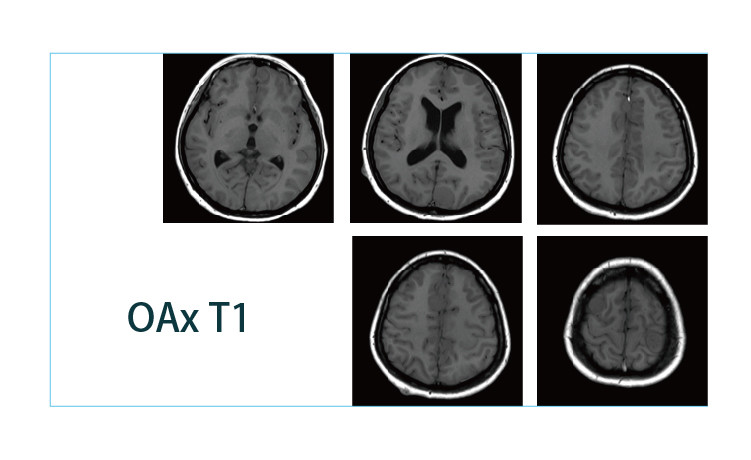

【朗润影像档案】20190412磁共振影像病例结果讨论

【朗润影像档案】磁共振影像病例分享(编号20190412)